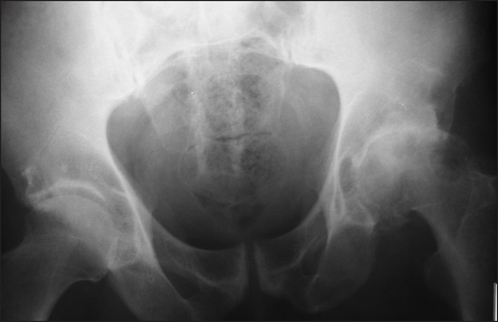

Figure 26.2 Osteoarthritis Anteroposterior X-ray of the hip showing the features of osteoarthritis. The left side is more severely affected than the right; note sclerosis, osteophyte formation and asymmetrical joint space narrowing.